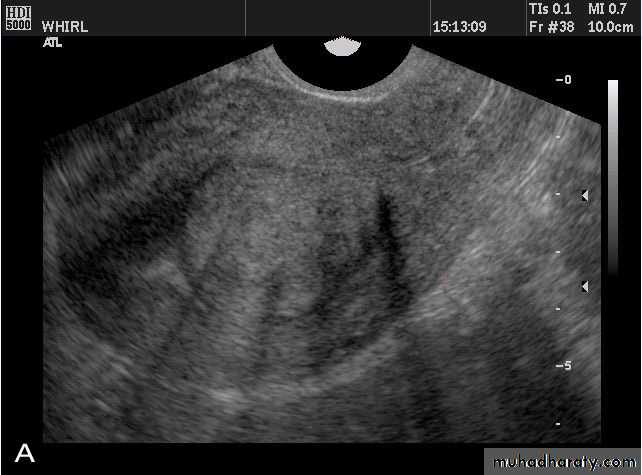

Fibroids (leiomyomata)• Intramural leiomyomata are frequently visualized. Examples of fibroids which compromise the contours of the endometrial cavity are shown (A–D). Refraction artifacts resulting from tissue density interfaces and the texture of the fibroids often aid in their identification.

• Fibroids (leiomyomata)

• Intramural leiomyomata are frequently visualized. Examples of fibroids which compromise the contours of the endometrial cavity are shown (A–D). Refraction artifacts resulting from tissue density interfaces and the texture of the fibroids often aid in their identification.• Fibroids (leiomyomata)

• Intramural leiomyomata are frequently visualized. Examples of fibroids which compromise the contours of the endometrial cavity are shown (A–D). Refraction artifacts resulting from tissue density interfaces and the texture of the fibroids often aid in their identification.Congenital anomalies of uterus